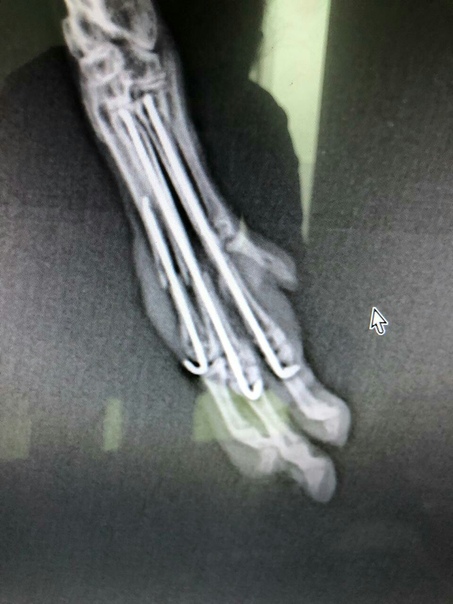

Chinchilla, 5 months, 320g, bone fracture of the metatarsus a week ago.

It's time to get the qualification of a microsurgeon ...